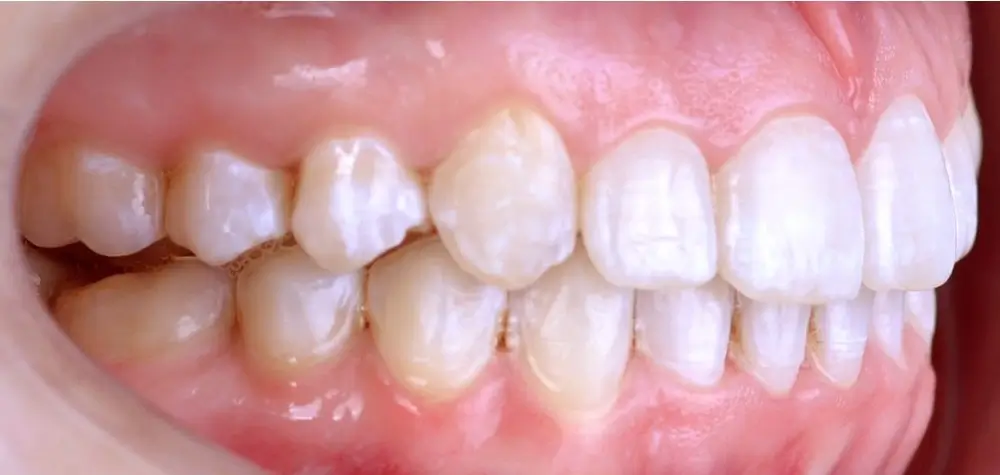

Кейс 1

Количество кап ВЧ 25

Количество кап НЧ 25

ДО

ПОСЛЕ